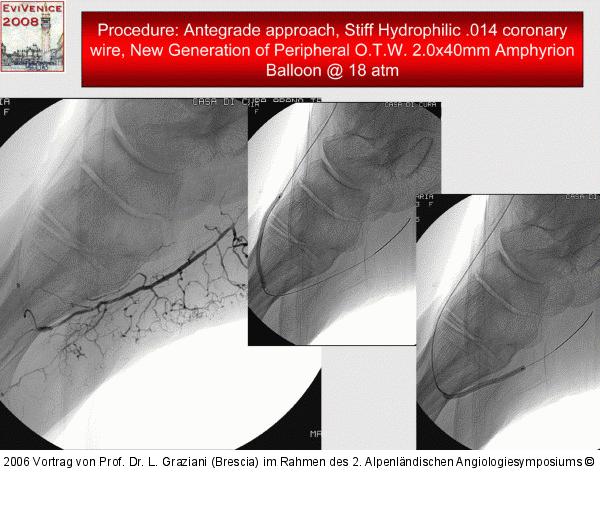

Vortrag von Prof. Dr. L. Graziani (Brescia) im Rahmen des 2. Alpenländischen Angiologiesymposiums

PTA of the foot arteries in diabetics: Extremities Extreme Angioplasty

Abbildung 63: P.O.B.A.